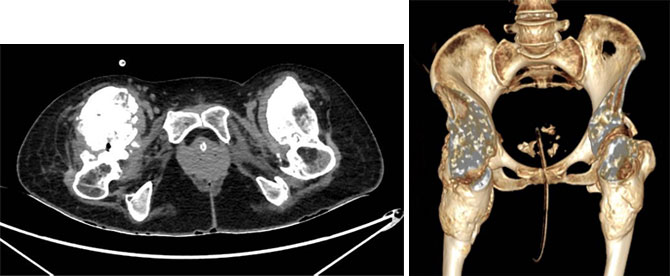

2020年,38岁的华人马女士(化名)在泰国遭遇了一场严重的车祸,腰1椎体水平以下双下肢全瘫,当时在泰国手术治疗,双下肢瘫痪并没有改善,这场意外给她的生活带来了巨大的变化。由于双下肢瘫痪以及车祸造成的髋关节周围血肿,患者双侧髋关节出现骨化性肌炎。多年来马女士一直在国内多家康复医院康复锻炼,但双髋关节骨化性肌炎仍然逐渐加重,髋关节活动度进行性下降,屈曲明显受限,平卧角度现已降至约20°。马女士只能躺在床上或轮椅上,无法坐起来,饮食起居需要别人帮助,生活质量极为低下。3年来,马女士辗转国内、国外,遍访多家医院,都没有解决她髋关节僵直的问题。

为了给马女士制定最适合的治疗方案,张余主任邀请了影像科、放疗科、烧伤整形科、麻醉科、ICU、康复科等多学科专家进行会诊、制定了个性化方案:首先,在手术前24小时内,对病灶进行低剂量的放射治疗,以减少髋关节骨化性肌炎出血及缩小病灶;其次,在手术过程中,切除髋关节周围的异位骨,改善关节活动度,并进行充分的止血处理;最后,在术后的两周内,髋关节需要保持相对静止,第三周开始进行康复训练。考虑到双侧髋关节骨化性肌炎严重,且异位骨量巨大,考虑术中出血多,张主任团队决定分两次手术。由于右侧髋关节异位骨巨大,髋关节活动更差,张主任决定先给患者做右侧的手术,等患者术后恢复良好后再做另一侧。

2023年7月14日,马女士接受了右侧髋关节骨化性肌炎切除术和髋关节成形术。手术非常成功,术中去掉大部分限制髋关节活动的异位骨,出血也不多。术后马女士的病情稳定,恢复良好。仅仅1周后,她成功出院,进一步康复锻炼。第一次手术的效果很好,右侧髋关节的屈曲度已经达到了90度。受此鼓舞,马女士欣然决定进行另一侧的手术。于是,在2023年9月19日,马女士第二次入院接受手术治疗。同样,医疗团队在术前24小时对病灶进行了低剂量的放射治疗。手术非常顺利,张余主任团队成功切除了病灶。术后,马女士转入系统而科学的康复锻炼。